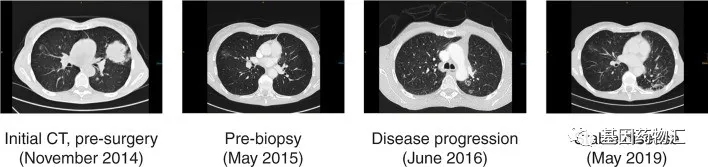

患者女性,62岁,有长期吸烟史,2014年11月偶然确诊为肺腺癌,其中左上肺叶的肿块直径6.4厘米,双肺多发磨玻璃结节,最大的直径达到1.8厘米。

患者通过基因检测评估了常见EGFR突变(18~21外显子),显示阴性,ALK荧光原位杂交和ROS1免疫组化也都是阴性,因此在术后选择了辅助化疗(卡铂+长春瑞滨)。但用药四个周期之后,CT复查肺部局灶性磨玻璃影反而增大了!随后的活检显示,患者已经复发。

如果按照前期的检测结果,那么患者肺癌常见的三大类突变都是阴性,当前的化疗方案又耐药,只能再更换更后线的化疗方案。但患者再一次完善了基因检测,这次确认,为EGFR外显子20插入突变,也就是我们常说的ex20ins。

自确认了这一点之后,患者后续的治疗之路就比较顺畅了。患者开始接受阿法替尼的治疗,逐渐减量,维持了10个月的病情稳定之后逐渐进展。随后患者接受了立体定向放射治疗,清除了共计3个病灶,并且继续接受阿法替尼的治疗,再次维持了1年的病情稳定;疾病在此进展之后,她又接受了针对新发病灶的一次放疗。

随后的近两年时间里,患者接受的3次针对血液的二代测序,都显示不再存在EGFR或其它类型的基因突变。过程中有一些小的波折,但患者二代阿法替尼治疗持续了共计超过5年,至报告时,病情仍然保持着稳定,ECOG评分长期为0分,患者体能状况非常良好!